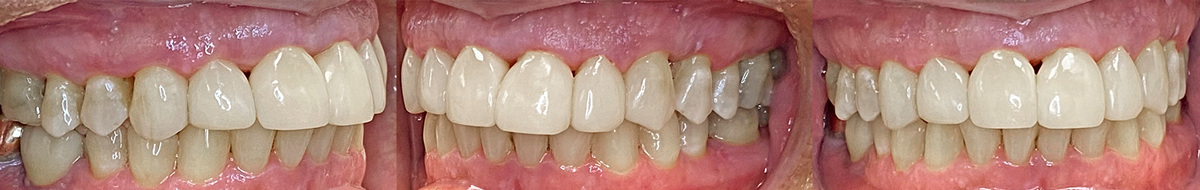

Résultats finaux

La méthode Bioclear permet à la résine composite chauffée de s'intégrer sans effort sur les surfaces radiculaires d'une manière qui n'irrite pas le parodonte. Bien au contraire, la fermeture des triangles noirs favorise la croissance papillaire jusqu'à 1 mm en repositionnant le point de contact apicalement et en le rapprochant de l'os crestal (Fig. 12). Dans l'ensemble, cette méthode permet au clinicien de répondre aux attentes du patient en matière de rajeunissement minimalement invasif de son sourire et de sa fonction, tout en réalisant cela en une seule séance. L'entretien parodontal doit être poursuivi par le patient et un suivi professionnel effectué tous les 3 mois.

FIG. 12

6 mois post-opératoire. Le déplacement apical du point de contact entre 11 et 21 favorise la croissance de la papille jusqu’à 1 mm.